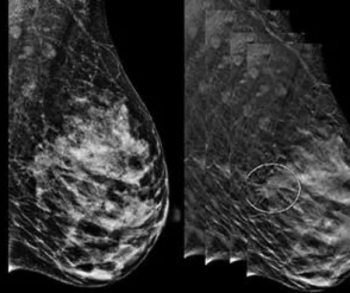

In a large study of nearly 100,000 women, researchers found that the combination of digital breast tomosynthesis (DBT) and synthesized mammography had more than triple the detection rate for invasive breast cancer in extremely dense breasts in comparison to digital mammography alone.

Women who had enhancing lesions associated with low-energy findings were more than twice as likely to have malignancy in comparison to those who had enhancing lesions without low-energy findings.

The review of breast cancer screening guidelines from the United States and abroad summarized current recommendations on modalities, intervals, and screening age considerations.